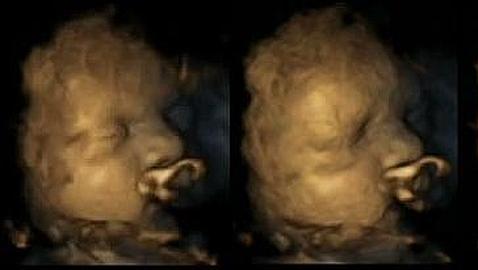

La investigación revela al fin cómo fumar durante el embarazo produce daños en el feto e, incluso, retraso en el sistema nervioso. El estudio ha sido realizado mediante el análisis de las ecografías en 4 Dimensiones de unas 20 mujeres. Mediante su estudio, se ha podido averiguar que los bebés de las madres fumadoras se tocan mucho más la cara y la boca con sus manos que aquellos pequeños cuyas progenitoras no ingieren tabaco.

Usualmente, los fetos realizan estos movimientos de manera más habitual cuánto menos desarrollados están, lo que podría implicar que el tabaco retrasa la evolución del sistema nervioso central del bebé. Así pues, estos datos determinan que el tabaquismo puede ser gravemente perjudicial para los niños no nacidos cuando se hallan en el útero de sus madres. Por ello, y en un intento de lograr que las progenitoras abandonen esta mala costumbre, Reissland ha publicado las impresionantes imágenes en la revista «Acta pediátrica».

La ecografías fueron realizadas en fetos desde las 24 semanas de gestación, hasta las 36 (tanto de madres fumadoras como no fumadoras). A su vez, y como parte del estudio –hecho en la Universidad James Cook- se escogió a progenitoras que tomaran un promedio de 14 cigarrillos al día. Con todo, Reissland ya ha señalado que espera aumentar la muestra de esta investigación en los próximos meses. Todo, con el objetivo de averiguar si los cigarrillos afectan de forma permanente al sistema nervioso central de lo smás pequeños cuando aún no han nacido.